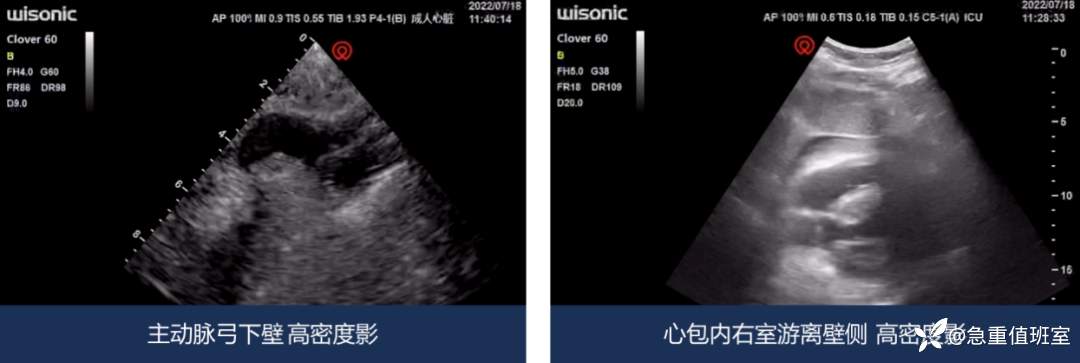

- 床旁心脏超声:主动脉夹层?心包积血?

图 2 床旁心脏超声